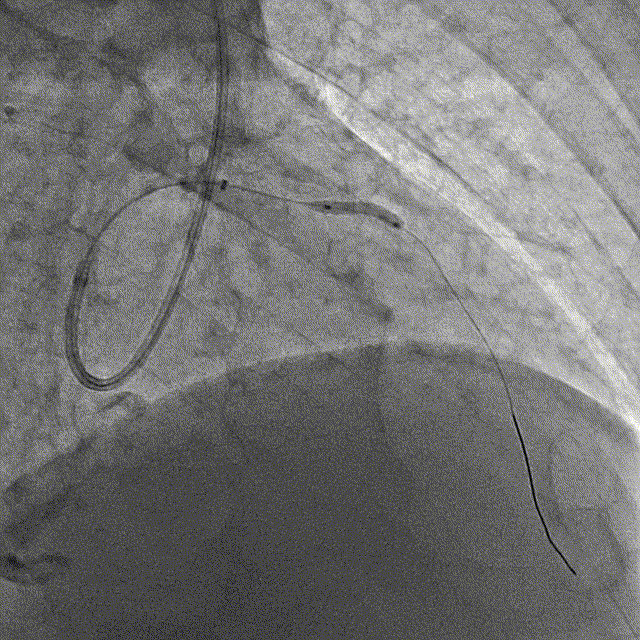

冠脉造影结果:LM外膜钙化,内膜不光滑,中段狭窄90%,TIMI3级。LCX外膜钙化,内膜不光滑,TIMI3级。RCA外膜钙化,内膜不光滑,近段狭窄80%,中段狭窄90%,可见破损斑块,TIMI3级。

冠脉内介入治疗